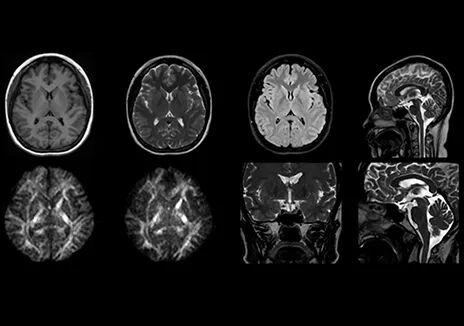

Fast BrainQuant快速定量一键脑技术对脑中风、脑外伤、血管畸形、神经退行性疾病等具有重要临床价值。该技术实现了在短时间内获得多达11种对比,包括定性和定量值在内的高分辨率三维全脑图像。